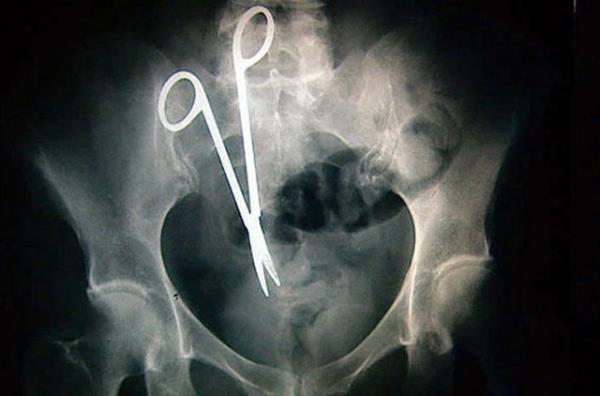

23. Hastanın midesinde unutulan bir makas...

Hastanın midesinde unutulan bir makas...